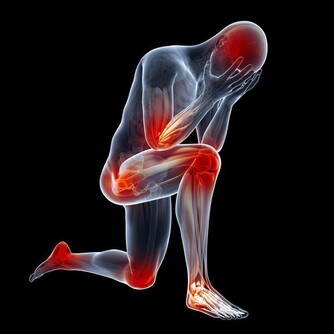

「養樹護根,養人護腳」。雙腳是運行氣血、聯絡臟腑、溝通內外、貫穿上下經絡的重要起始部位。

當腳部出現一些癥狀或者變化時,往往能反映出身體的某些健康問題。